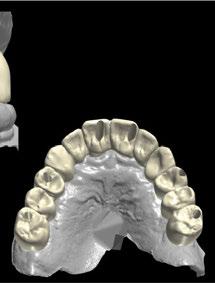

-Escáner intraoral mediante iTero Element™2 con el fin de obtener modelos digitales (archivos STL) (Figura 3).

Figura 3. Archivo STL inicial obtenido mediante iTero Element™2.

1. Planificación digital y diseño de la férula de cirugía guiada Tras analizar el caso y siguiendo los parámetros estéticos y funcionales, se realizó un encerado digital de la arcada superior mediante el programa de diseño 3D Exocad® (Figura 5), el cual se imprimió y validó junto al paciente mediante un mock-up (Figura 6 a-b).

A continuación, para la planificación de los implantes dentales y el diseño de la férula de cirugía guiada se usó la plataforma digital RealGUIDE®. Para ello se realizó el matching, por un lado, del archivo STL del encerado digital; y, por otro, del archivo 3D. De esta manera, se pudo analizar el tejido óseo residual apical a cada diente y la posición de la raíz respecto a las corticales vestibular y palatina. También se estudió la relación de los contornos óseos con los tejidos blandos y con la posición final de los márgenes cervicales de la restauración protésica, pudiendo así planificar la posición 3D correcta de los implantes. En esta primera fase se diseñó una férula quirúrgica para la elevación de seno bilateral a partir del software RealGUIDE™, que nos sirvió de guía para el diseño de las ventanas de acceso. Esta férula se imprimió con la impresora 3D Formlabs® (Figura 7)

A los 6 meses de cicatrización, se realizó un nuevo CBCT, obteniendo un nuevo archivo DICOM que alineamos con el STL del encerado. De esta manera, se planificó la posición de los implantes a 4 mm del margen de la restauración final y se diseñó y confeccionó la férula de cirugía guiada dentosoportada en 12-13 y 22-23, la cual imprimimos con la impresora 3D Formlabs®. El provisional

de carga inmediata lo diseñamos con el programa de diseño 3D Exocad® a partir del encerado y se imprimió también en clínica con la misma impresora 3D (Figuras 14-16).